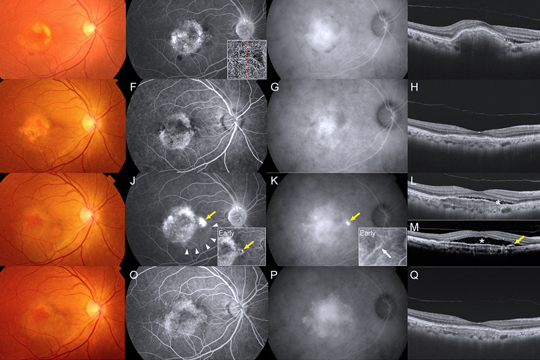

Центральная серозная хориоретинопатия

Центральная серозная хориоретинопатия проявляется отслоением нейроэпителия в области макулы. Основной причиной заболевания является дефект в мембране Бруха, что приводит к проникновению жидкости под сетчатку.